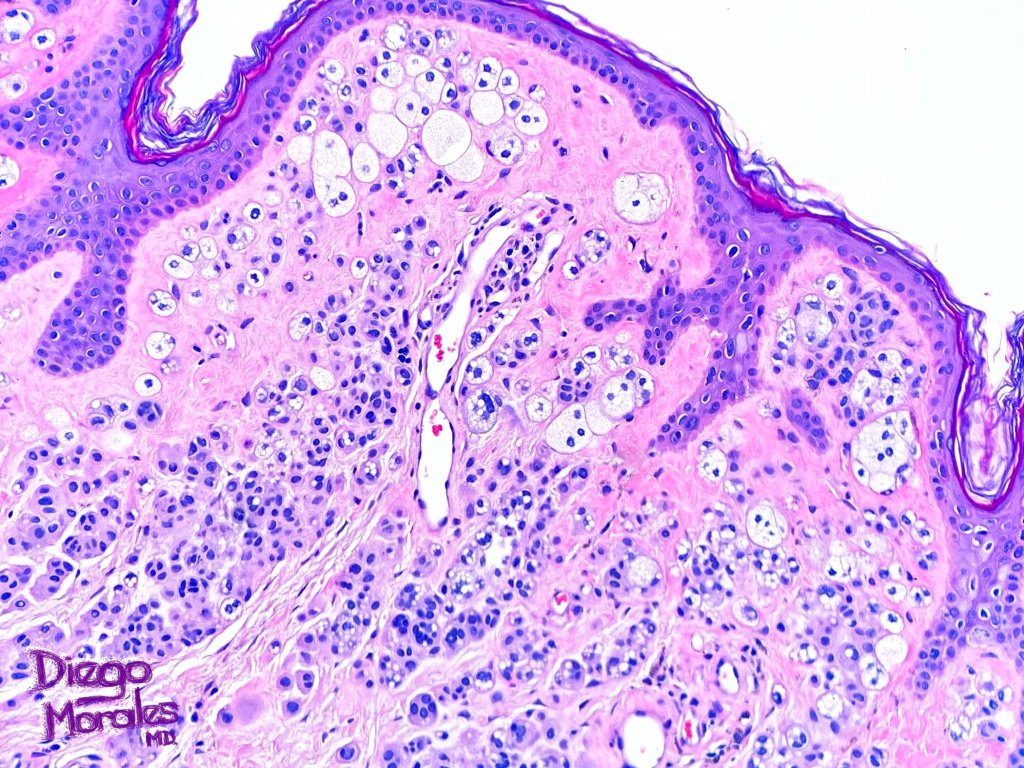

.Balloon cell change is most often seen in banal melanocytic nevi but it has also rarely been described in cellular blue nevus, dysplastic nevus, combined nevus, halo nevus & Spitz nevus. Lesions with <50% of balloon cells are sometimes described as nevi with balloon cells. Nevi with >50% balloon cells are described as balloon cell nevus.

.Balloon cell nevs genrally has uniform, hyperchromatic nuceli (as opposed to the vesicular nuclei with prominent nucleoli) seen in melanoma. Mitoses are absent.(In my experience, balloon cell melanoma is more common than balloon cell nevus).